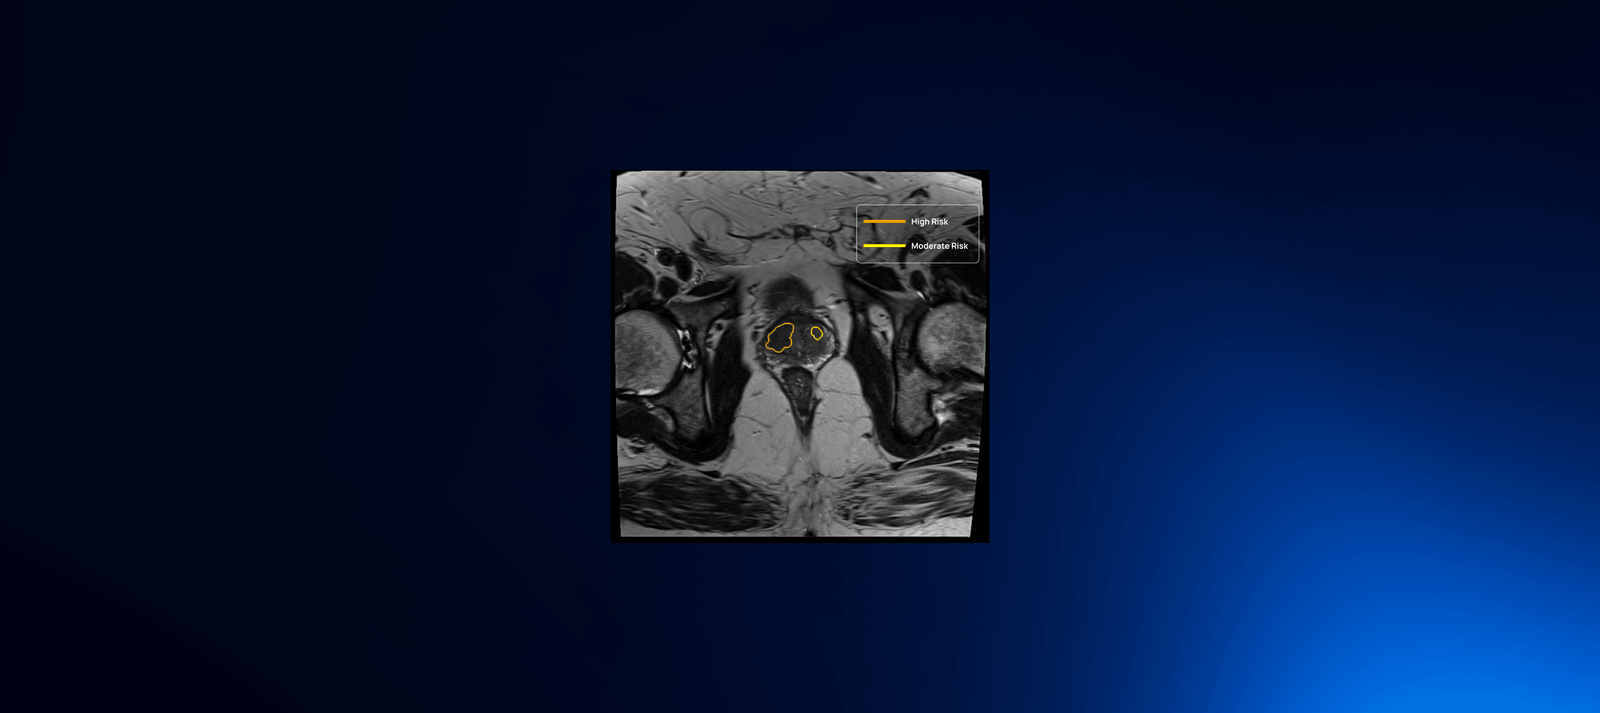

QP-Prostate is setting a new standard for accuracy, speed, and diagnostic precision. Its AI algorithm identifies and stratifies by likelihood intermediate and high-grade aggressive prostate cancer lesions, and provides a segmentation of the prostate. This allows Health Care Professionals to improve their diagnostic accuracy and fusion biopsy planning.

QP-Prostate automatically identifies and highlights prostate regions suspicious for aggressive prostate cancer, assigning each a confidence-based classification score.

Developed by Quibim, QP-Prostate excels in automating the segmentation of critical prostate regions, including the transition zone, peripheral zone and seminal vesicles. By streamlining these complex processes, the software not only aids in the interpretation of prostate MRI images, but also enables more accurate diagnoses. This combination of sophisticated AI-based analysis and user-friendly implementation makes QP-Prostate an invaluable tool in the hands of healthcare professionals, ensuring better patient outcomes through more reliable and detailed assessments.